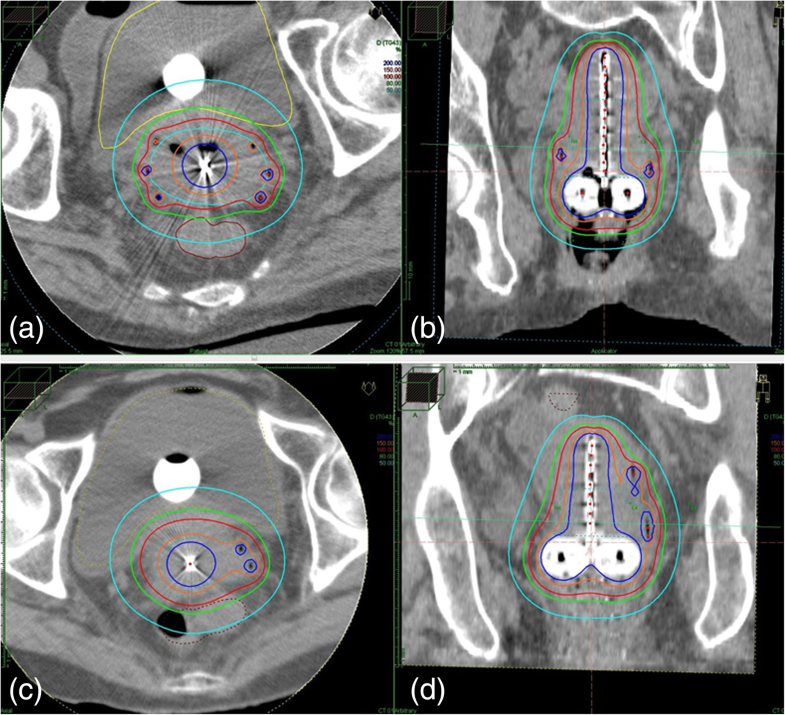

From www.brachyjournal.com

Contemporary imageguided cervical cancer brachytherapy Consensus Is Brachytherapy For Cervical Cancer Painful Brachytherapy for cervical cancer > follow up after brachytherapy > risks and side effects of brachytherapy > when will i have brachytherapy? You may have internal radiotherapy (brachytherapy) or external. You may be dealing with the effects of other treatments, such as. if you have your womb > if you do not have your womb > recovering from brachytherapy. Is Brachytherapy For Cervical Cancer Painful.

From www.frontiersin.org

Frontiers Combined Interstitial and Intracavitary HighDose Rate Is Brachytherapy For Cervical Cancer Painful if you have your womb > if you do not have your womb > recovering from brachytherapy > more information and support > also in this section: receiving ebrt is painless and the treatment typically lasts a few minutes. You may be dealing with the effects of other treatments, such as. You may have internal radiotherapy (brachytherapy) or. Is Brachytherapy For Cervical Cancer Painful.

Frontiers Combined Interstitial and Intracavitary HighDose Rate Is Brachytherapy For Cervical Cancer Painful brachytherapy can have a huge impact on your physical and emotional wellbeing. along with surgery and chemotherapy, brachytherapy, a type of radiation therapy, is a treatment option for cervical cancer. Individuals receiving ebrt often do so over several outpatient visits. brachytherapy and its effects can have a huge impact on your physical and emotional wellbeing. Brachytherapy for. Is Brachytherapy For Cervical Cancer Painful.

Threedimensional imageguided combined intracavitary and interstitial Is Brachytherapy For Cervical Cancer Painful You may have internal radiotherapy (brachytherapy) or external. brachytherapy and its effects can have a huge impact on your physical and emotional wellbeing. Individuals receiving ebrt often do so over several outpatient visits. brachytherapy can have a huge impact on your physical and emotional wellbeing. receiving ebrt is painless and the treatment typically lasts a few minutes.. Is Brachytherapy For Cervical Cancer Painful.

Threedimensional imageguided combined intracavitary and interstitial Is Brachytherapy For Cervical Cancer Painful brachytherapy and its effects can have a huge impact on your physical and emotional wellbeing. Brachytherapy for cervical cancer > follow up after brachytherapy > risks and side effects of brachytherapy > when will i have brachytherapy? along with surgery and chemotherapy, brachytherapy, a type of radiation therapy, is a treatment option for cervical cancer. Individuals receiving ebrt. Is Brachytherapy For Cervical Cancer Painful.